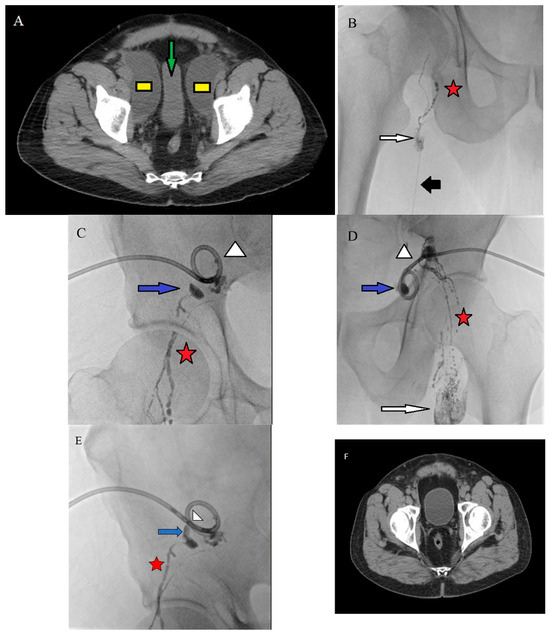

Endovascular Management of Iliac Hematoma Associated with May–Thurner Syndrome Using Mechanical Thrombectomy and Bare-Metal Stenting: A Case Report

Background/Objectives: May–Thurner syndrome (MTS) is a common cause of iliofemoral deep vein thrombosis (DVT). Venous bleeding associated with MTS is extremely rare and has been reported mainly as spontaneous iliac vein rupture (SIVR) with retroperitoneal or iliac hematoma. Additionally, standardized treatment strategies have [...] Read more.

Background/Objectives: May–Thurner syndrome (MTS) is a common cause of iliofemoral deep vein thrombosis (DVT). Venous bleeding associated with MTS is extremely rare and has been reported mainly as spontaneous iliac vein rupture (SIVR) with retroperitoneal or iliac hematoma. Additionally, standardized treatment strategies have not yet been established. Herein, we report a case of an iliac hematoma associated with MTS that was successfully treated with endovascular mechanical thrombectomy and bare-metal stenting. Case Presentation: A 69-year-old man presented with acute swelling and pain in the left lower extremity. Computed tomography angiography demonstrated extensive iliofemoral DVT and an iliac hematoma adjacent to the left common iliac vessels, without definite evidence of iliac vein rupture. Initial conservative management with anticoagulation therapy was selected as the patient was hemodynamically stable and showed no active bleeding. However, follow-up imaging one week later revealed persistent DVT with interval enlargement of the hematoma. Pelvic arteriography excluded an arterial bleeding source. Endovascular treatment was performed, including mechanical thrombectomy using the AngioJet system and bare-metal stent placement to restore venous outflow. Follow-up imaging revealed complete thrombus resolution, hematoma regression, and sustained stent patency. Conclusions: Iliac hematomas associated with MTS may occur without definite radiological evidence of iliac vein rupture. In selected hemodynamically stable patients, an individualized endovascular strategy focused on venous outflow restoration using the AngioJet system and bare metal stents may be a feasible treatment option. Full article